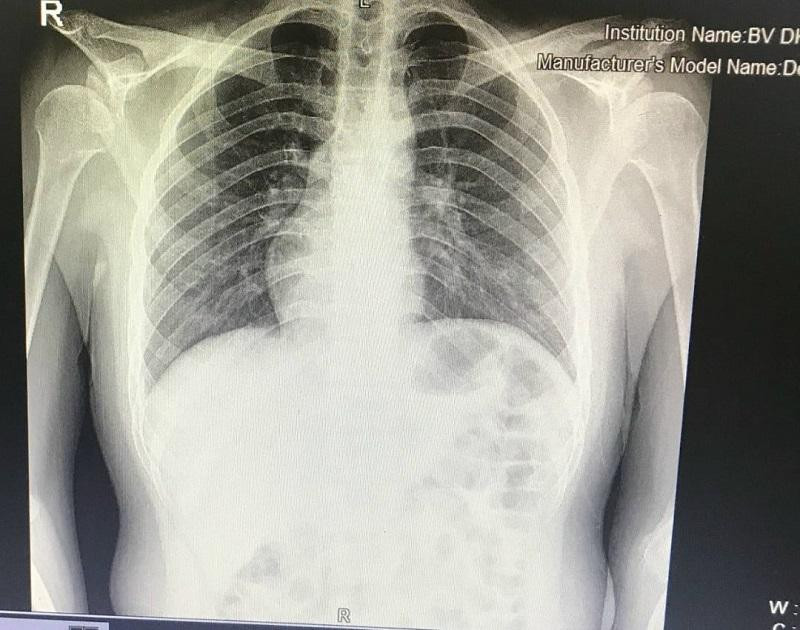

| Hình ảnh chụp Xquang cho thấy nam thanh niên có trái tim nằm bên phải lồng ngực |

Qua thăm khám và kết quả chụp chiếu, bệnh nhân được chẩn đoán Viêm ruột thừa. Điều khiến các bác sĩ rất bất ngờ đó là hình ảnh trái tim trong lồng ngực bệnh nhân H. ở vị trí đảo ngược so với người bình thường và phủ tạng đảo ngược hoàn toàn, lỗ tiểu thấp, có dị tật dính đầu chi.